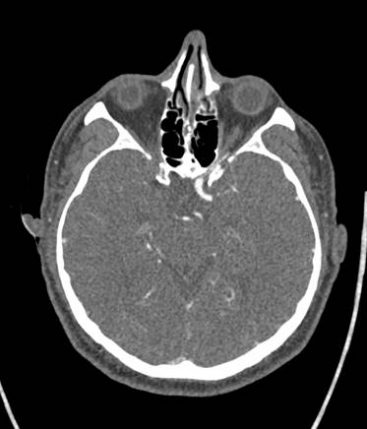

CT Perfusion maps (T-MAX) showing hypo-perfused posterior cerebral artery and AChA territories on the right side.

24-hr CT showed a small lesion in the anterior portion of the right thalamus and a marginal lesion in the adjacent right internal capsule